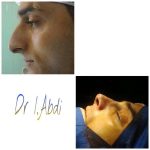

– متخصص جراحی فک , پلاستیک صورت و بینی

جراحی فک , پلاستیک , صورت وبینی

جراحی ترمیمی و زیبایی فک و صورت و جمجمه و گردن